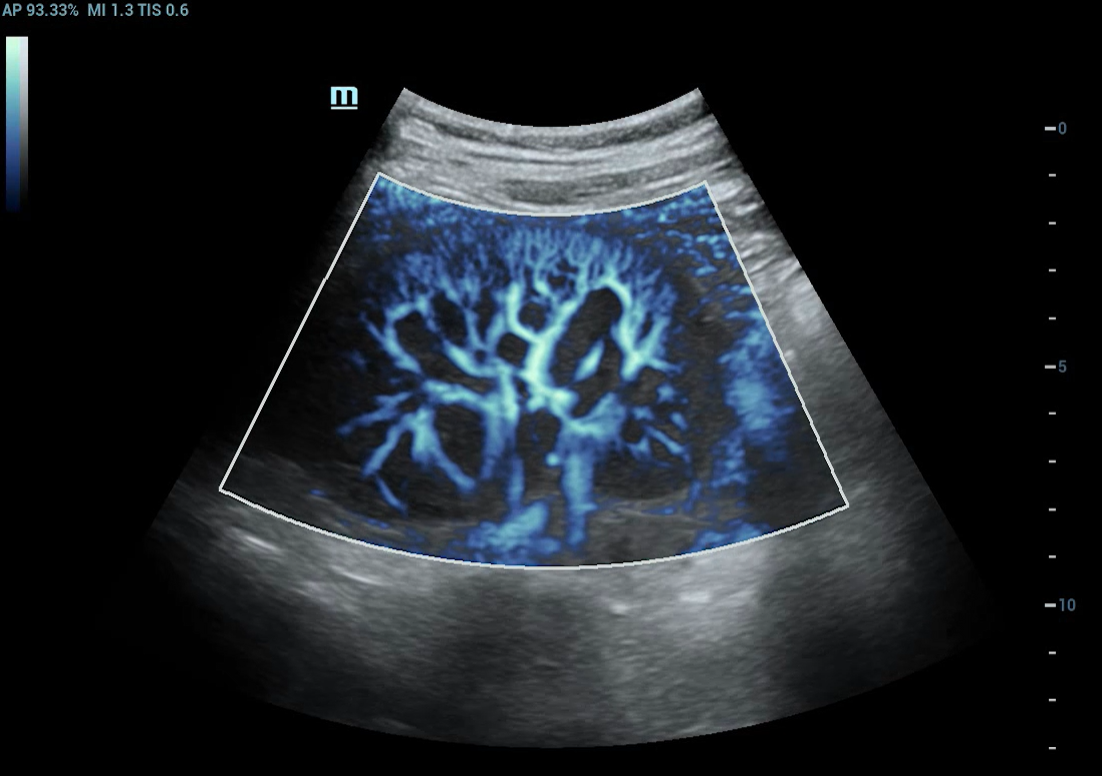

Технология SlowflowHD — новое решение для оценки микрокровотока. Она отображает слабые, медленные потоки в мельчайших сосудах, помогая видеть структуру плаценты, хориона, сосудов мозга плода и эндометрия без использования контраста. SlowflowHD даёт врачу дополнительный уровень детализации, позволяя выявлять васкуляризацию даже в сложных клинических случаях.

Технология SlowflowHD применяется для исследования матки и яичников, головного мозга плода, плаценты